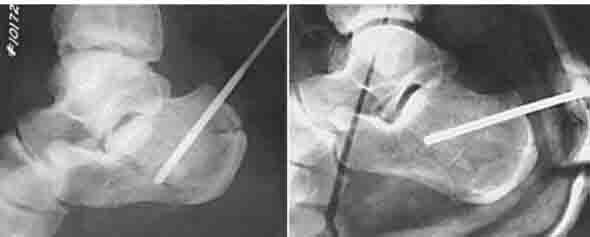

ORIF -единственный способ, позволяющий восстановить конгруэнтность подтаранного сустава, и «при всем богатстве выбора другой альтернативы нет (с)». Вопрос совершенно не в низведении бугра пяточной кости и восстановлении угла Белера – это элементарно делается и аппаратом, и даже еще более простым способом – в бугор в направлении ссади вперед вводится толстая спица, используя ее, как джойстик, бугор низводится, спица проталкивается еще глубже ( картинка из Кэмпбелла). Вот только «проваленную» заднюю суставную поверхность пяточной кости без ORIF and bone grafting не восстановить